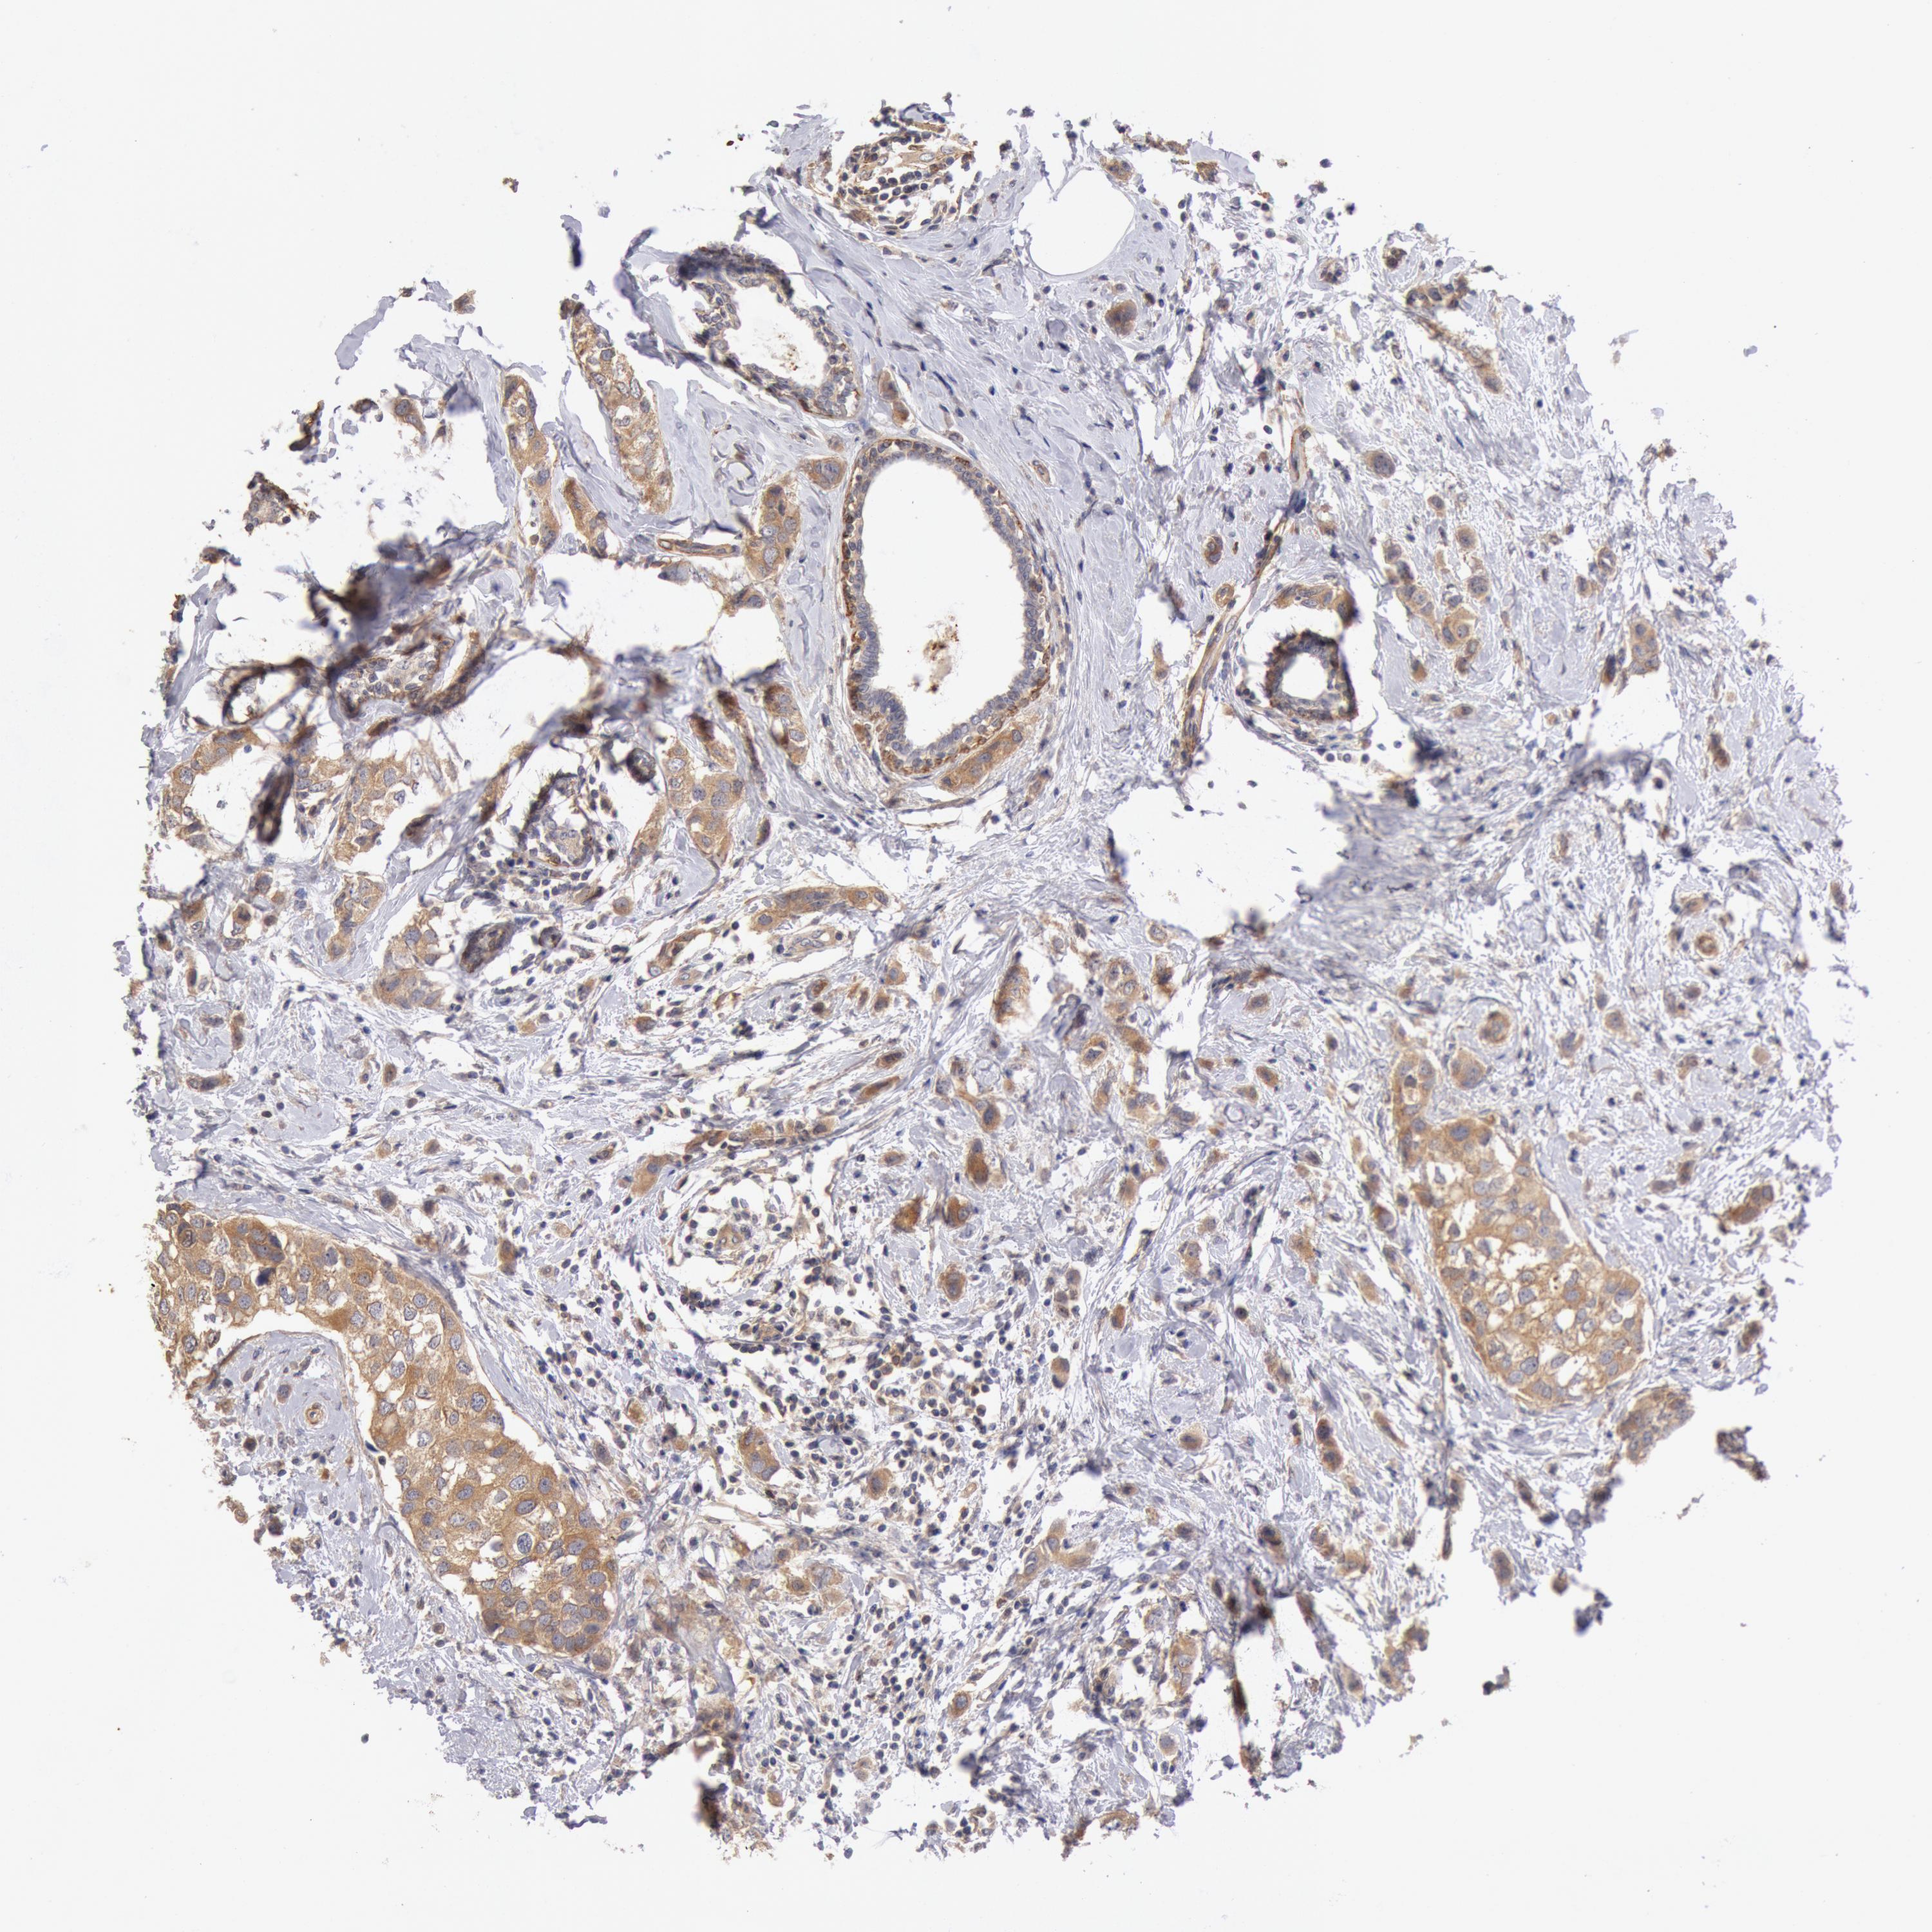

CANCER BREAST CANCER Show tissue menu

BRCA TCGA BRCA VALIDATION PROTEIN EXPRESSION